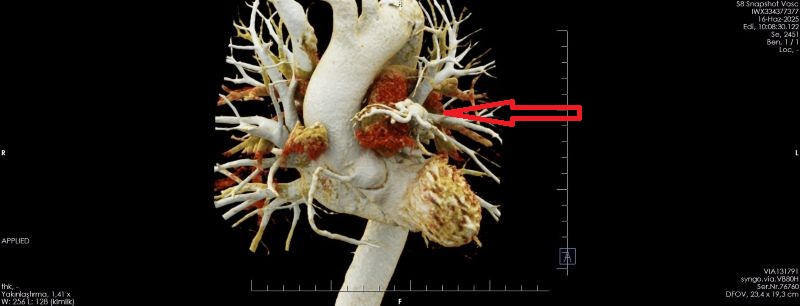

OLGU:

Koroner arterin pulmoner artere füstülizasyonu ile Koroner BT Anjiyografi ile demosterize edilmiş olgu örneğidir.